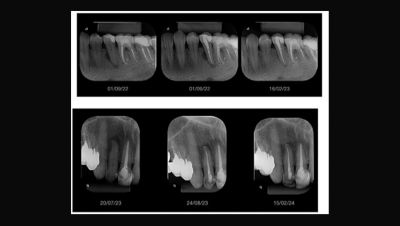

ProRoot Bio Sealer delivers a very high short-term healing rate and provides more stable radiographic visibility over time (compared to the leading bioceramic sealer).2